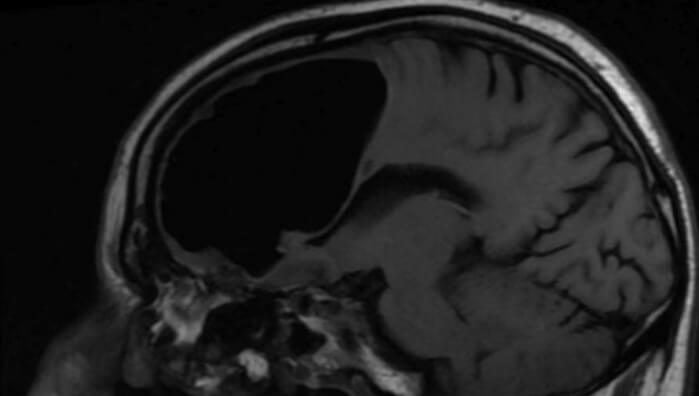

Idoso tem um buraco de 9 cm dentro do cérebro

O homem de 84 anos, que é da Irlanda do Norte, foi…